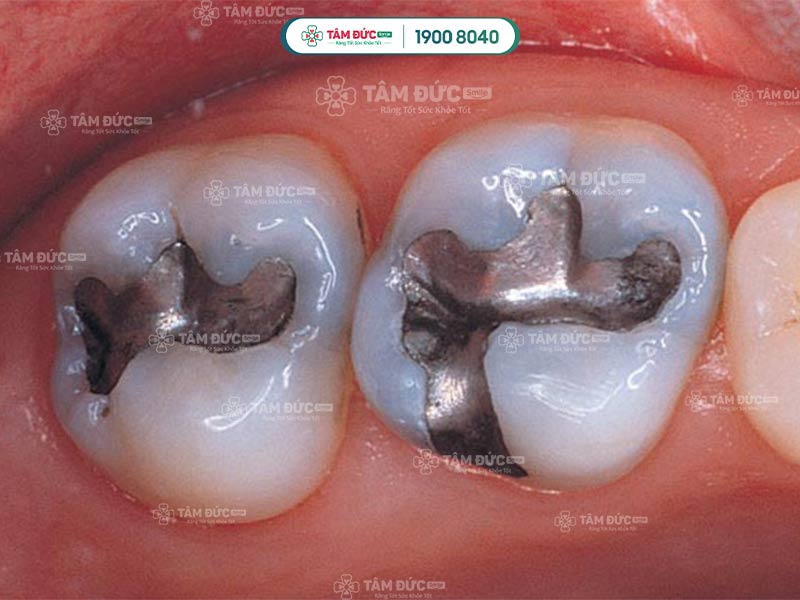

Bác sĩ giải đáp rằng: Quý khách không thể dùng thuốc tẩy trắng răng cho răng đã trám. Vì thuốc tẩy trắng răng chỉ có tác dụng trên men răng thật. Thuốc tẩy trắng không thay đổi màu sắc của vật liệu trám răng. Nếu vẫn bỏ qua cảnh báo mà tẩy trắng cho răng trám, nhiều rủi ro khác sẽ xảy ra. Cụ thể, có nhiều trường hợp thuốc tẩy trắng tiếp xúc với vật liệu trám răng đã gây ra phản ứng Oxy hoá. Chẳng hạn như: Chất liệu trám Amalgam trở nên đậm màu hơn, gây ê buốt răng khi tiếp xúc với thuốc tẩy trắng.

Như vậy, Quý khách tuyệt đối không nên tẩy trắng cho răng trám tại nhà hoặc tại nha khoa. Nếu thực hiện, màu sắc giữa răng trám và răng bình thường sẽ bị chênh lệch. Điều này làm cho thẩm mỹ bị ảnh hưởng nghiêm trọng hơn.